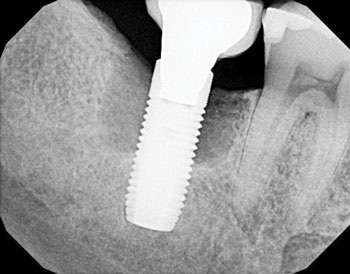

The following radiographs demonstrate representative surgical cases treated with a laser-assisted protocol, illustrating resolution of peri-implant radiolucency, stabilization of crestal bone levels and improved bone density patterns over time.

Fig. 1 illustrates tooth #29, restored with a dental implant placed 18 years prior, which presented with vertical osseous defects on both the mesial and distal aspects. Follow-up radiographic evaluation demonstrates adequate osseous fill on the mesial and distal aspects following therapy.

Fig. 1: Initial and follow-up radiographs of dental implant at site #29.